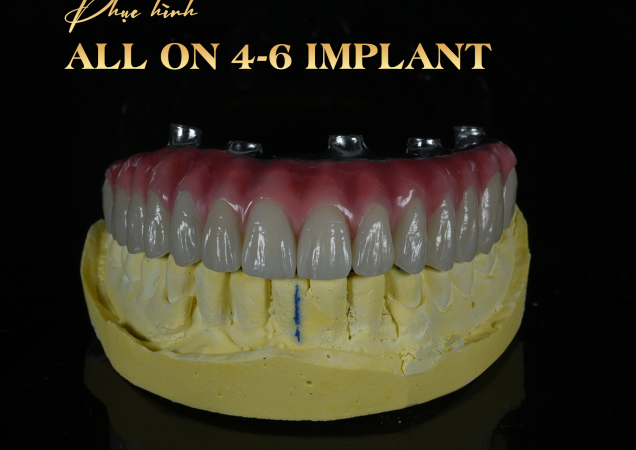

ALL ON 4 – 6 IMPLANT

All-on-4 và All-on-6 là kỹ thuật cấy ghép Implant toàn hàm tiên tiến, giúp phục hồi toàn bộ răng mất chỉ với 4 hoặc 6 trụ Implant. Phương pháp này mang lại hàm răng cố định, thẩm mỹ và ăn nhai vững chắc gần như răng thật.

– Trên các trụ này, gắn cầu răng cố định gồm 10–14 răng, phục hình toàn bộ hàm trên hoặc hàm dưới.

– Thẩm mỹ cao: Thiết kế ôm sát nướu, màu sắc tự nhiên, giúp gương mặt trẻ trung hơn.